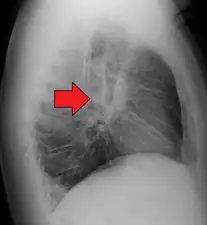

| Chest X-ray showing the typical nodularity of sarcoidosis, predominantly in the hila of the lungs. | |

Hilar adenopathy especially on the person's left (AP CXR)

Hilar adenopathy especially on the person's left (lateral CXR)